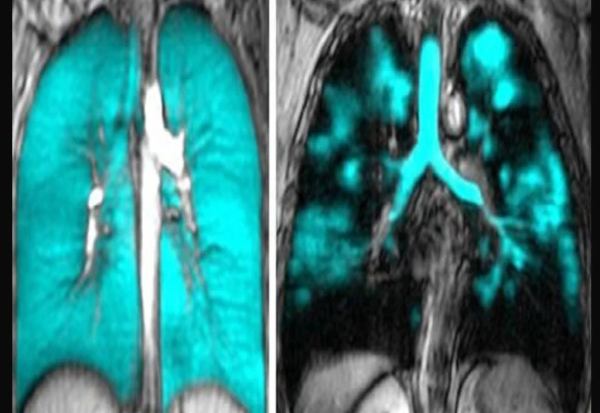

Но, новата техника на снимање сега јасно го откри изворот на проблемот со дишењето.

Скеновите ја покажуваат големата штета што може да ја предизвика ковид-19 на нашите нежни респираторни органи. Без разлика дали се работи за самиот вирус или одговорот на телото на него, некој механизам ефикасно ја намалил функцијата на белодробните крвни садови на пациентите, откинувајќи голем дел од најмалите каде што се одвива многу важната размена на гасови.

Истражувачите, предводени од физичарот Александар Матесон од Западниот универзитет, им наложиле на 40 доброволци – 34 со постакутен ковид-19 синдром и 6 без долг ковид – да вдишат ксенон. Гасот резонира со карактеристична фреквенција под МРИ, овозможувајќи им на истражувачите да ја набљудуваат активноста на дишните патишта и крвните садови во реално време.

Васкуларното оштетување се рефлектира со скеновите со МРИ; и другите скенирања ги потврдуваат абнормалностите во најдобрите крвни садови во нашите бели дробови.